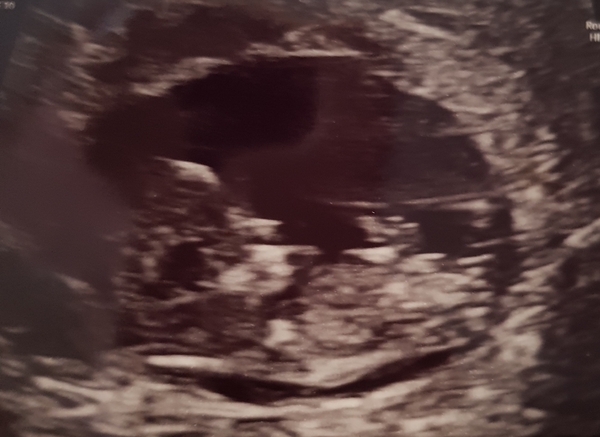

Had my scan this morning!

They put me 4 days behind so slightly too small to do the screening. 10w 6days. So have to go back in 3 weeks but all is ok so far :)

Congrats @Treaclepie19 lovely picture :)

I had my scan yesterday- all was well too, thankfully, and I’m 11+6 today. New due date of 6 April Smile. I was very nervous.

Congrats treaclepie lovely scan pic!

Hi ladies, I had my scan yesterday and all was well ☺️ new due date 5th April, 3 days later than I thought

I love these scan photos. So lovely to finally see isn't it!

Congrats @treaclepie, @fraggle and @annie, lovely pics there!

Lovely to see all the scan pics! I can't wait to have the first scan but I've probably still got about 3/4 weeks till mine! It's all so exciting!